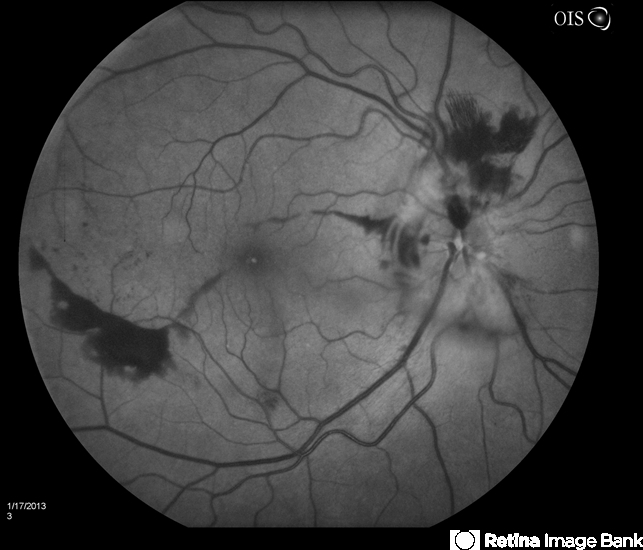

- Diabetic Papillitis

- Patient was about to undergo surgery for CNS aneurysm. Patient woke up with little spots which never cleared up. Patients VA was 20/30-OD and 20/40-OS. Both eyes appeared to have disc edema with hemorrhages in the right eye. Ordered a CT of the brain to make sure the aneurysm didn't ruptured.